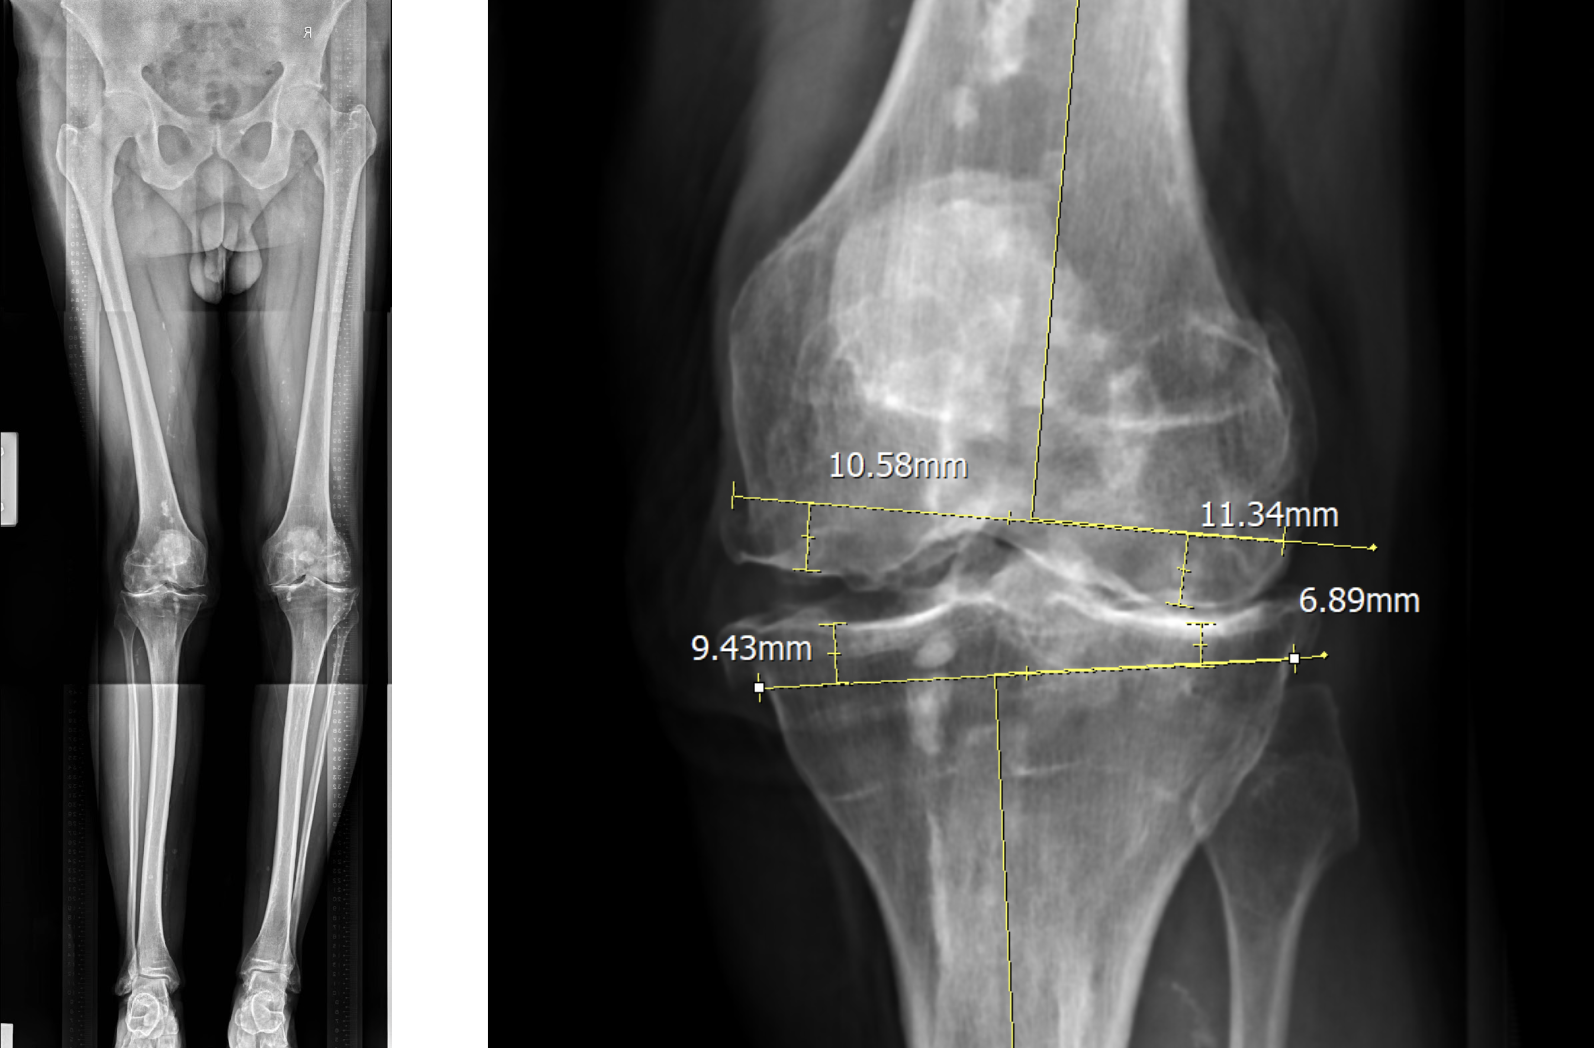

การผ่าตัดด้วยเครื่องมือมาตรฐานในการผ่าตัดเปลี่ยนข้อเข่าเทียมด้วยวิธีมาตรฐาน ผู้ป่วยจะได้รับการถ่ายภาพรังสีแบบเต็มขา (Full Leg Film) ซึ่งครอบคลุมตั้งแต่ข้อสะโพกจนถึงข้อเท้า ภาพรังสีนี้จะใช้สำหรับวางแผนการผ่าตัด โดยศัลยแพทย์จะประเมินทิศทางของแนวแรง แนวที่ต้องตัดกระดูก และความหนาของกระดูกที่จะตัดอย่างละเอียดในระดับมิลลิเมตร

เมื่อเข้าสู่ขั้นตอนการผ่าตัด เครื่องมือจะช่วยศัลยแพทย์ในการตัดกระดูกตามแนวที่วางแผนไว้ ความหนาของกระดูกที่ตัดออกจริงควรใกล้เคียงกับค่าที่คาดการณ์ไว้มากที่สุด เพื่อให้การวางข้อเข่าเทียมมีความแม่นยำและสอดคล้องกับสรีรวิทยาของผู้ป่วย วิธีการนี้ถือเป็นวิธีที่มีความแม่นยำและให้ผลลัพธ์ที่ดีในการผ่าตัดข้อเข่าเทียม